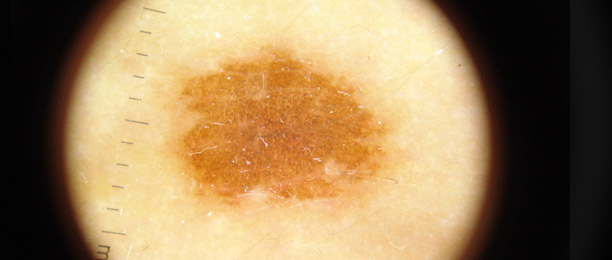

Lo studio e la diagnosi delle neoformazioni cutanee attraverso strumenti specifici indicati per un'analisi delle caratteristiche strutturali superficiali e profonde delle varie neoformazioni cutanee: dermatoscopia, dermalite a luci fotocromatiche, mappatura nevica con videodermatoscopia digitale.

Al fine di una corretta diagnosi dei nevi, e dunque di un'efficace prevenzione da forme tumorali, è indispensabile visionare in profondità i caratteri di ogni formazione nevica. Ciò è reso possibile dall'utilizzo del dermatoscopio e dalla concomitante mappatura nevica, con l' eventuale rimozione chirurgica o laser di: